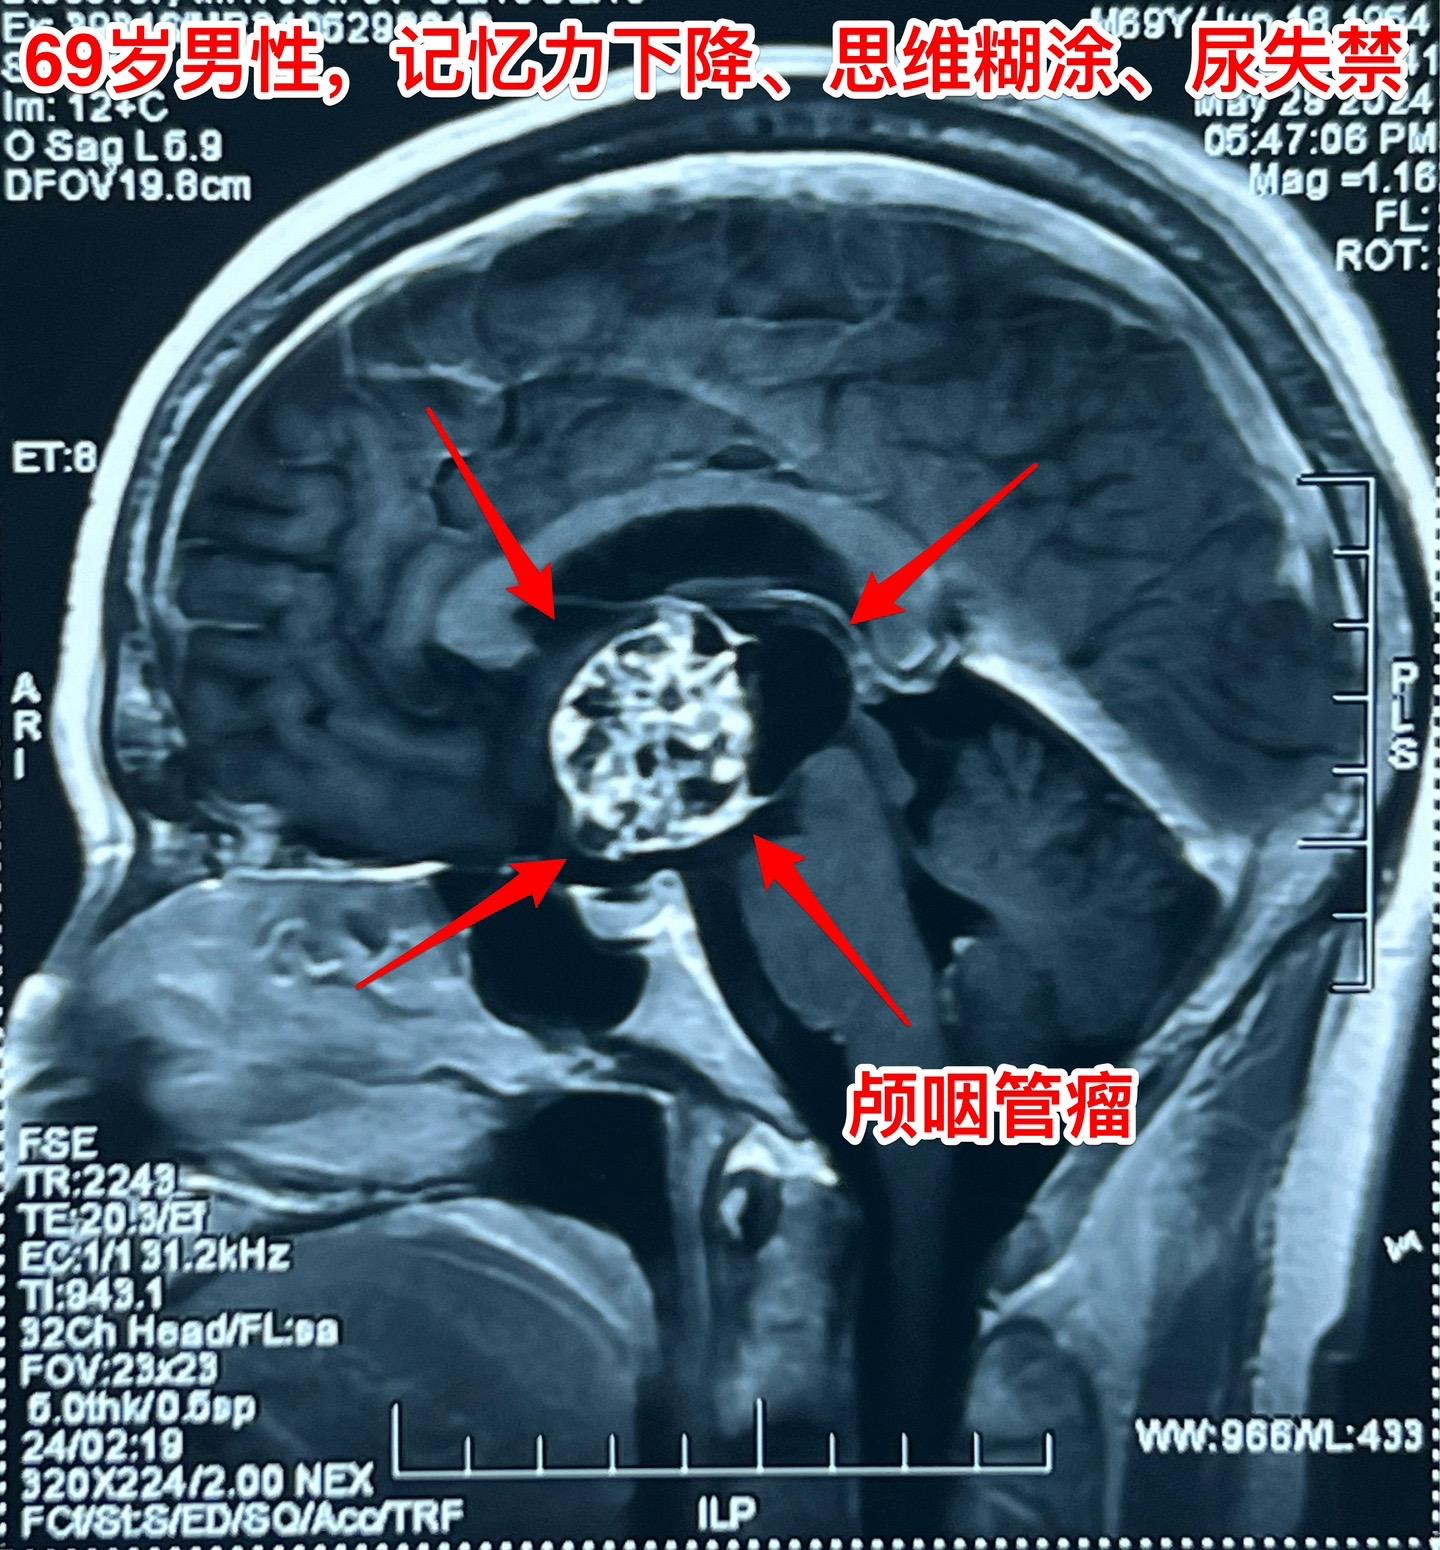

69岁发现颅咽管瘤还能作手术吗?69岁的南通市老人近半年出现记忆力差、糊涂。4月份出现尿失禁,到医院检查才发现病根儿是颅咽管瘤,肿瘤体积大,导致了脑积水。第一步在当地医院先作了脑室-腹腔分流术,治疗脑积水,尿失禁的症状有改善。 但是老人的身体很虚弱。还不能下地行走。这样的身体状态是不能承受切除颅咽管瘤这样的大手术的。 老人的女儿随后和我加后,我给予老人补充激素后,老人的身体状况才逐步改善,慢慢地能下地走路了。 不能不佩服这家人的勇气和爱心[强][强]!